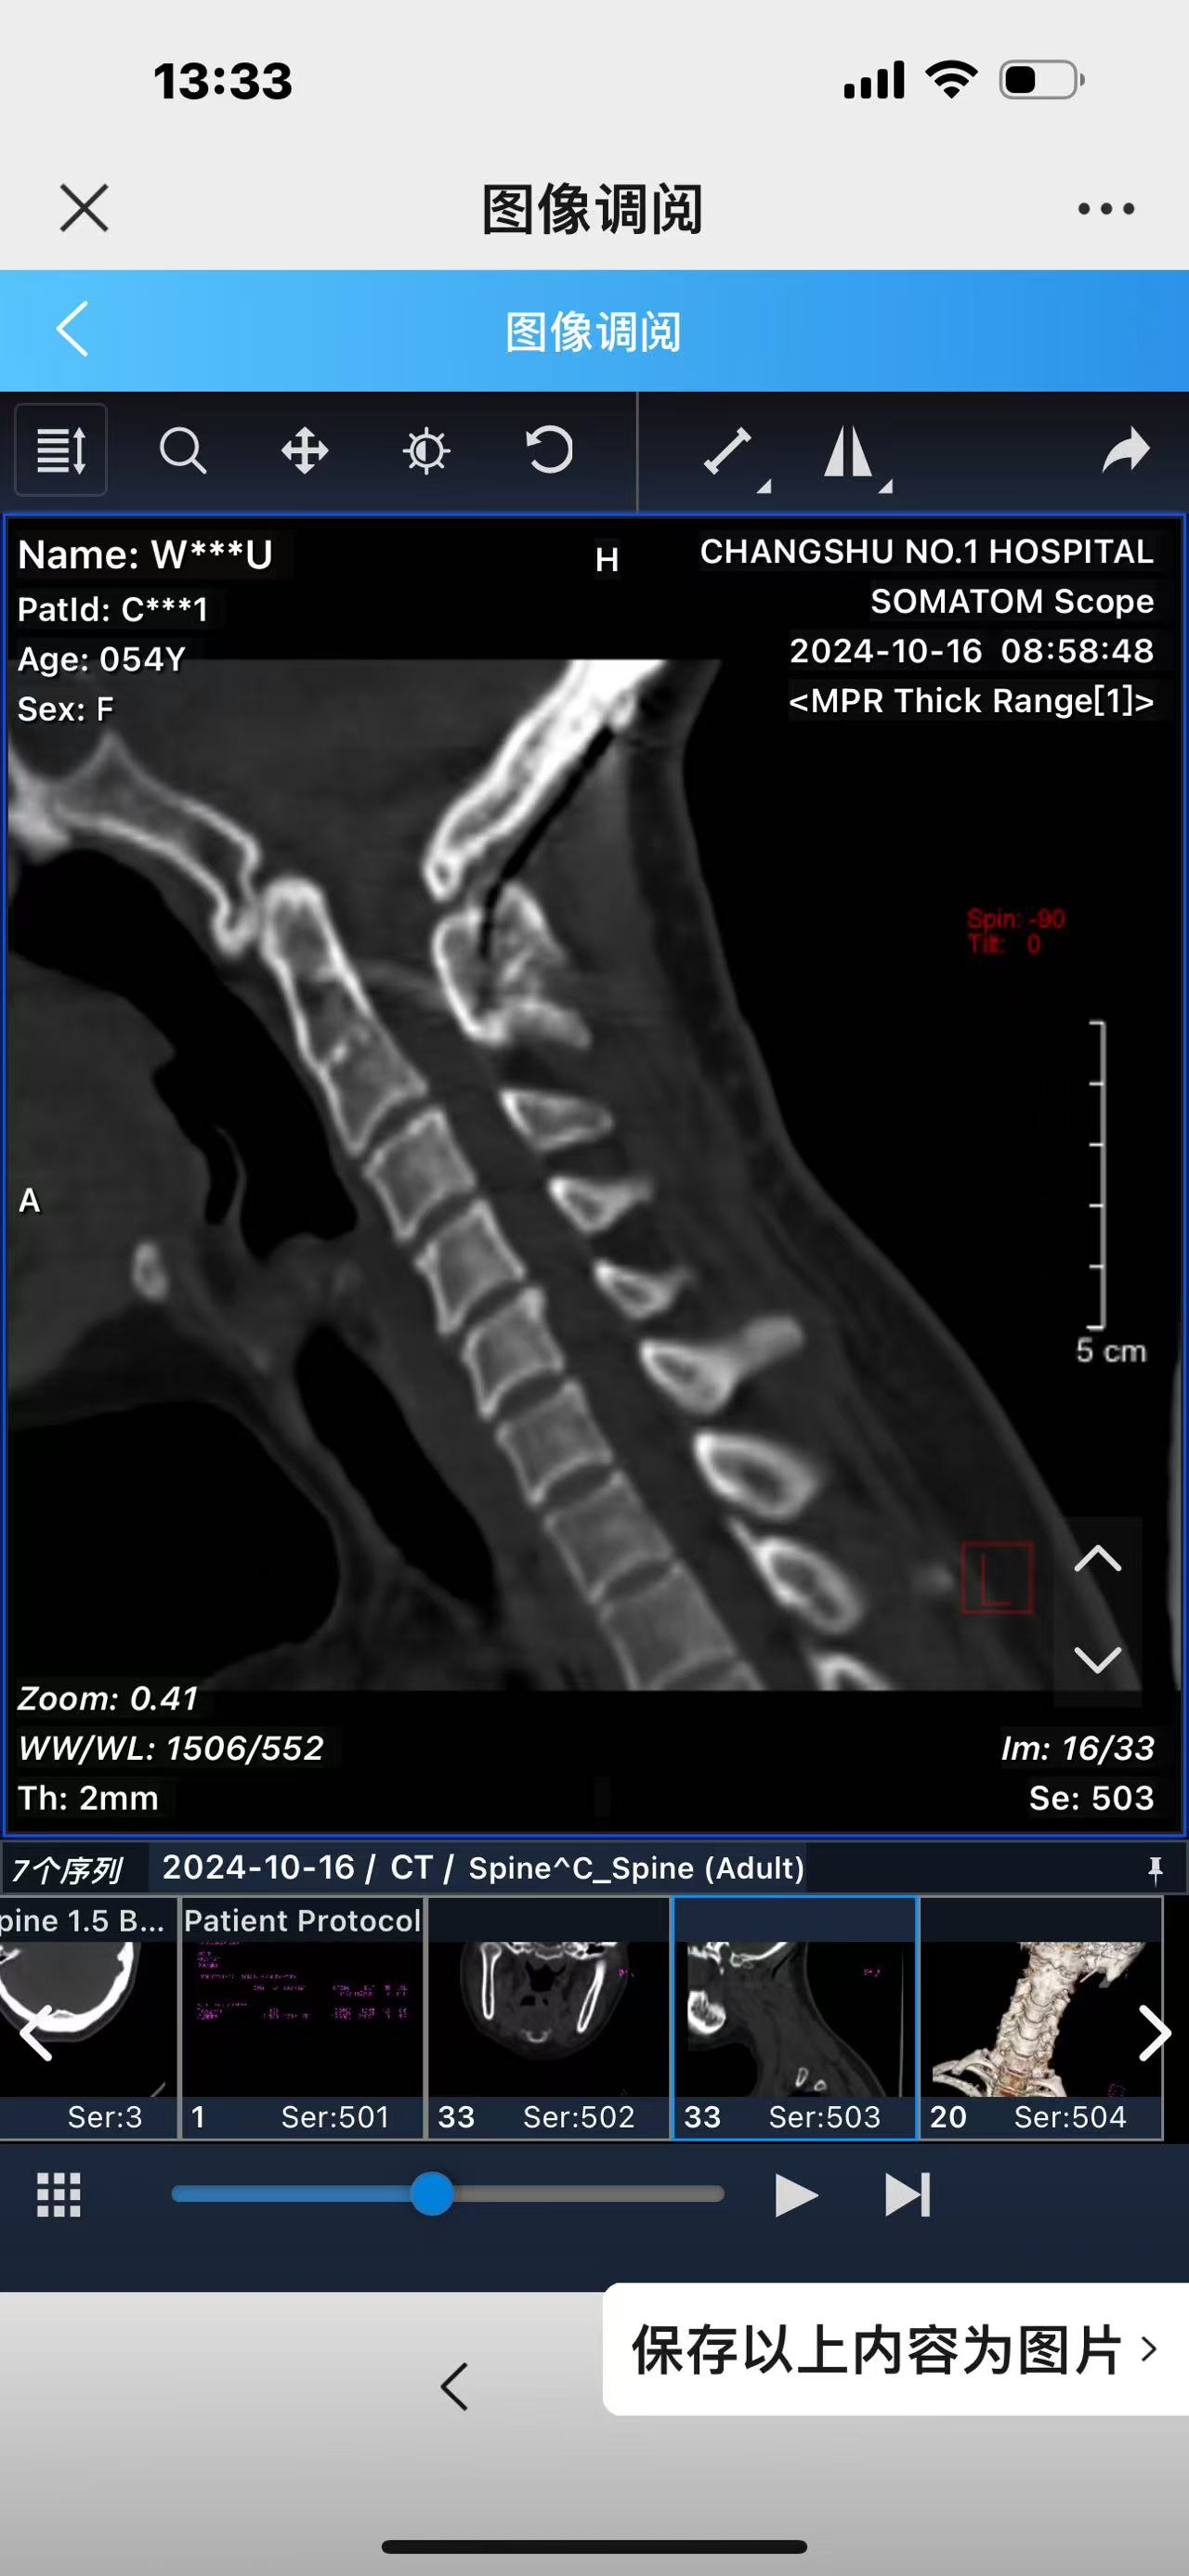

• 诊断:寰枢椎脱位,颅底凹陷

• 影像:

• 术后影像: